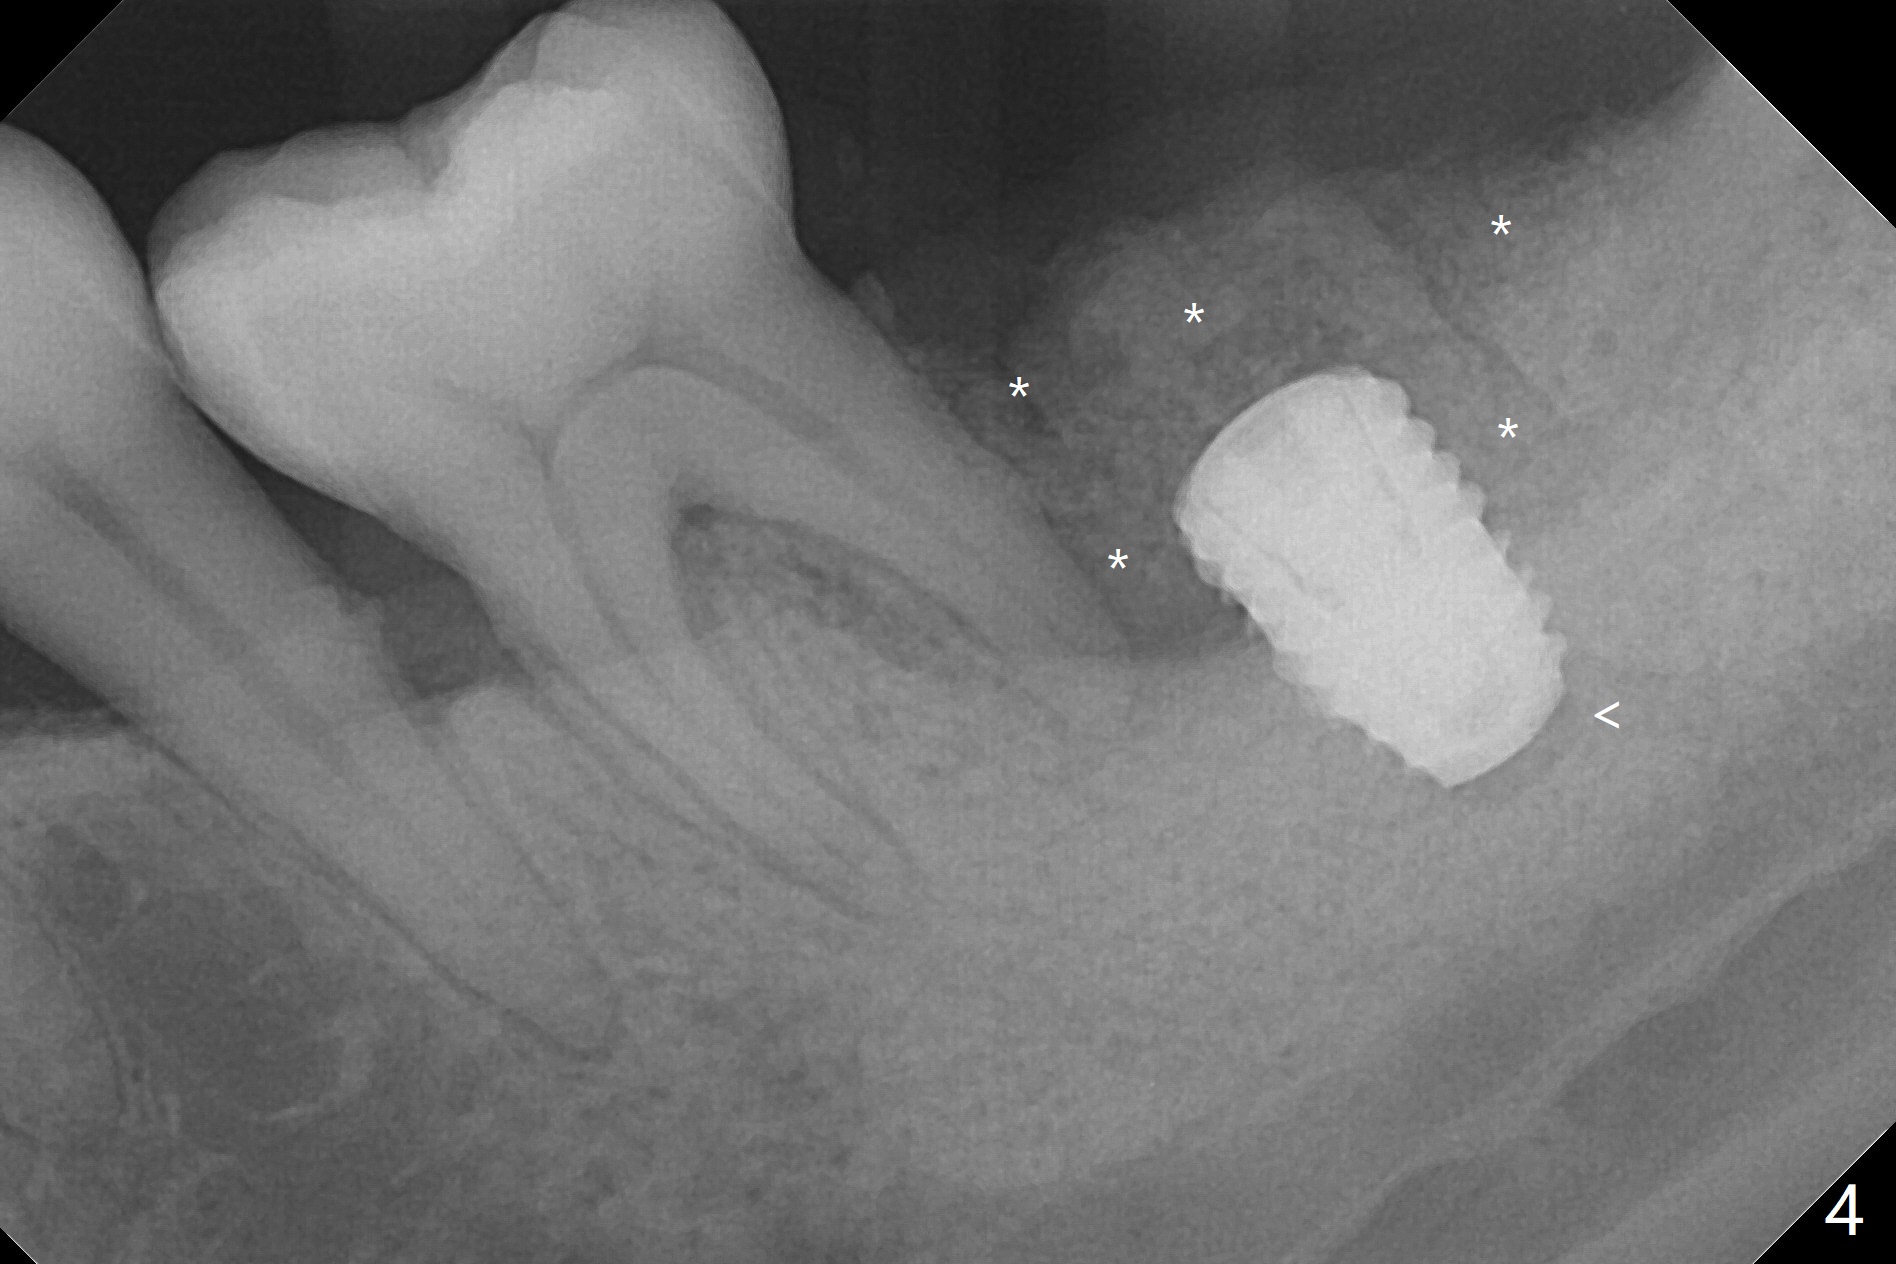

Socket shield (partial extraction therapies) is going to be conducted in this case to form a substitute buccal plate of the 2nd molar (Fig.1 *). The apex of the shield that contacts the 4.5x10 mm dummy implant cannot be removed because of poor access (Fig.2 * (12 mm offset)). Due to high bone density, a 4.5 mm drill has to be used in order to place a 5x7.3 mm definitive implant (Fig.3). In spite of the fact that the implant seems to be completely seated, the implant is ~ 1 mm supracrestal lingually. After implant removal, a 4.5x11.5 mm drill cannot reach the depth due to high bone density. 800 RPM instead of 50 RPM may help. When the implant is reseated, it appears to be .5 mm deeper than before clinically, although it looks incompletely seated in X-ray (Fig.4 <). The insertion torque is 60 Ncm. Allograft mixed with PRF is placed around the implant with cover screw, particularly mesiolinguodistal (Fig.4 *). The sockets of #17 and 18 are approximated with the help of 2 piece of PRF and collagen plug. The wound dehisces 9 days postop (Fig.5,6), although asymptomatic. Forced closure of the sockets with suture seems unnatural. An immediate provisional should have been fabricated. CT shows possible loss of part of bone graft (Fig.7). Regraft seems necessary in the appointment of uncover. Antibiotic is prescribed for another week. The gingiva seems healthy around the exposed healing screw 16 days postop (Fig.8). After debridement, the healing screw is then changed to a 4.5x5 mm healing abutment. The majority of the bone graft is lost without immediate provisional in 4 months (Fig.9 * (<: socket shield)). Then a 5.5x5 mm healing abutment is inserted for impression next appointment. A 5.2x4.5(4) mm cemented abutment is placed before impression (Fig.10). With socket shield (Fig.11 ^), the buccal gingiva looks more keratinized than the lingual one (Fig.12 *). Photos are taken immediately pre-cementation. Socket shield (*) covers the implant and abutment buccally (Fig.13 CT taken immediately pre-cementation).